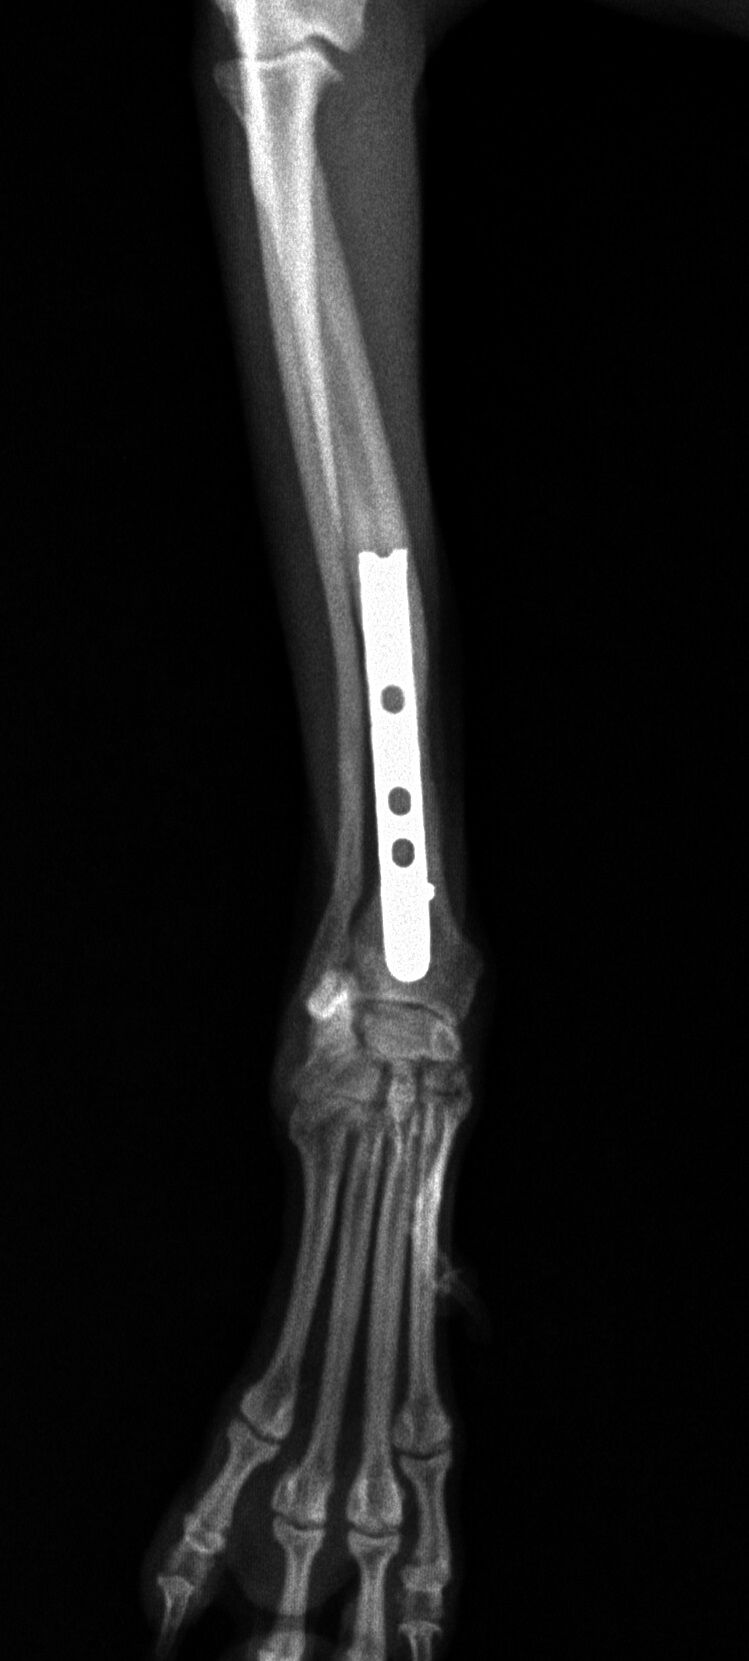

その後、1か月普通に生活していました。レントゲンを撮ったところ、骨は十分に増生していたので、心配ないと判断しプレートを取りました。

プレート除去前

プレート除去後

プレート除去後は何の問題もなく生活しています。うまくいきました。